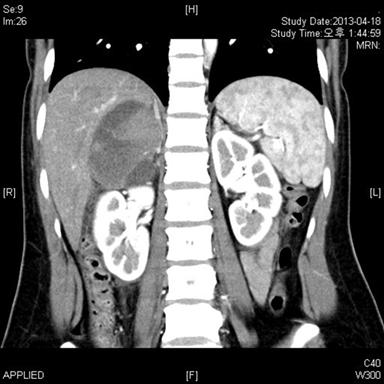

Computed tomography (CT) revealed a well-defined oval mass with speckled calcifications suggesting multiple phleboliths (Figure 2). The left adrenal gland was unremarkable, and there was no lymph node enlargement. Her abdomen and pelvis seemed normal except for what seemed to be a cystic lesion in the uterus for which further gynecologic ultrasonography was scheduled. On magnetic resonance images (MRI), the mass showed a heterogeneous area with an internal hemorrhagic component suggesting pheochromocytoma or adrenal cortical carinoma. However, endocrinologic examination did not reveal any abnormalities. It was still ambiguous to identify the nature of the mass correctly and evidence with MRI and CT seemed insufficient to rule out malignancy. Therefore further evaluations were pursued and positron-emission tomography (PET) with 18F-fluorodeoxyglucose (18F-FDG) was carried out.

Figure 2. Enhanced computed tomography of the abdomen showed a well-defined oval mass in the right adrenal gland. Images in the arterial phase showed irregular enhancement and tiny calcifications inside. |